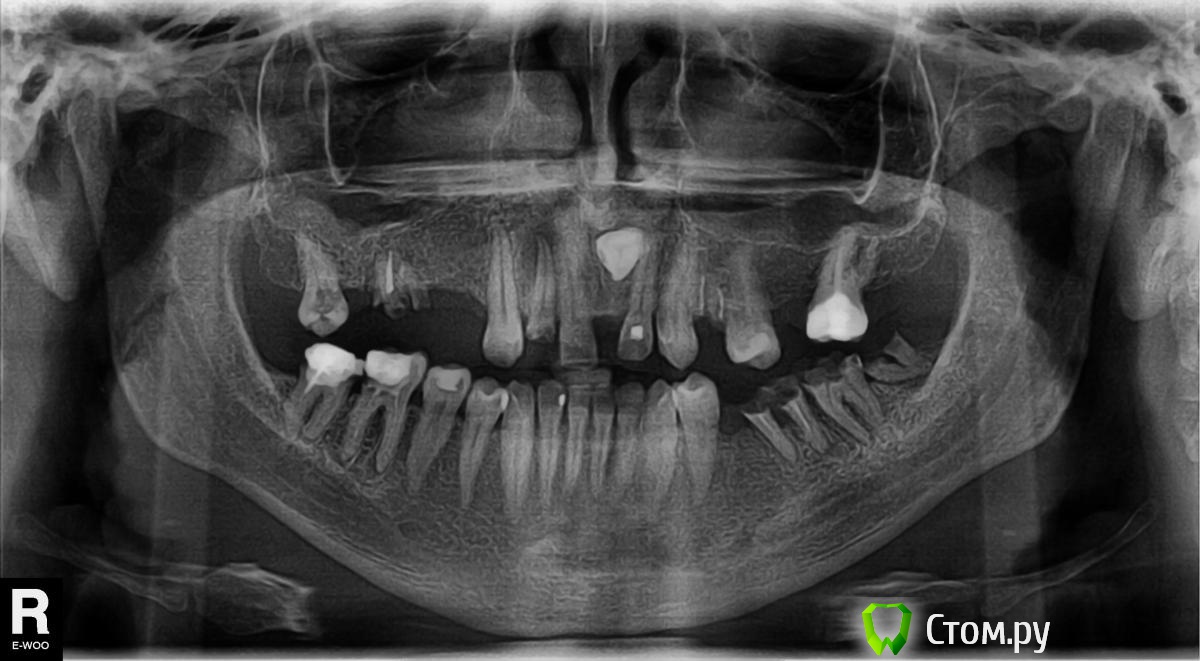

Dobry Опубликовано 12 ноября, 2013 Поделиться Опубликовано 12 ноября, 2013 Добрый день. Давно не был у стоматолога, и вот когда попал - картина оказалась следующей: Вопрос стоит по поводу левой нижней стороны, где буду удалять 3 оставшихся корешка и на их место наверное надо ставить импланты, а вот какие виды имплантов и каких фирм- ВОТ ЭТО ВОПРОС. Кто то говорит, что имплант - это как авто на котором едешь за грибами, на количество собранных грибов - не влияет. )))) Но почитал старую темку в разделе "для врачей" про беларусские и русские импланты - и что то отпало желание смотреть в эту сторону. Деньги все равно буду собирать на сие мероприятие (или занимать) Вопрос в том, что сейчас провожу лечение переднего зуба и с 3 мя левыми нижними корешками решать надо уже в течении 2х недель(удалять). Я так понимаю, что просто удалить их для имплантации нельзя, а вот как надо - не понимаю. (сразу имплант надо ставить или все же ждать полтора месяца?, или как то удалять с сохранением кости? (в оообщем темный лес)) В общем какой процесс это должен быть?Заранее спасибо. Ссылка на комментарий

IvanK Опубликовано 12 ноября, 2013 Поделиться Опубликовано 12 ноября, 2013 Здравствуйте.Я бы советовал посетить стоматолога-Ортопеда для составления плана лечения. Заниматься нужно всем... Удаление:18?, 16, 21, 24, 27?, 38,37,36, 46?, 47?..Санация.Съемное протезирование или протезирование с опорой на имплантаты. Искать нужно не имплантат, а Врача.. Ссылка на комментарий